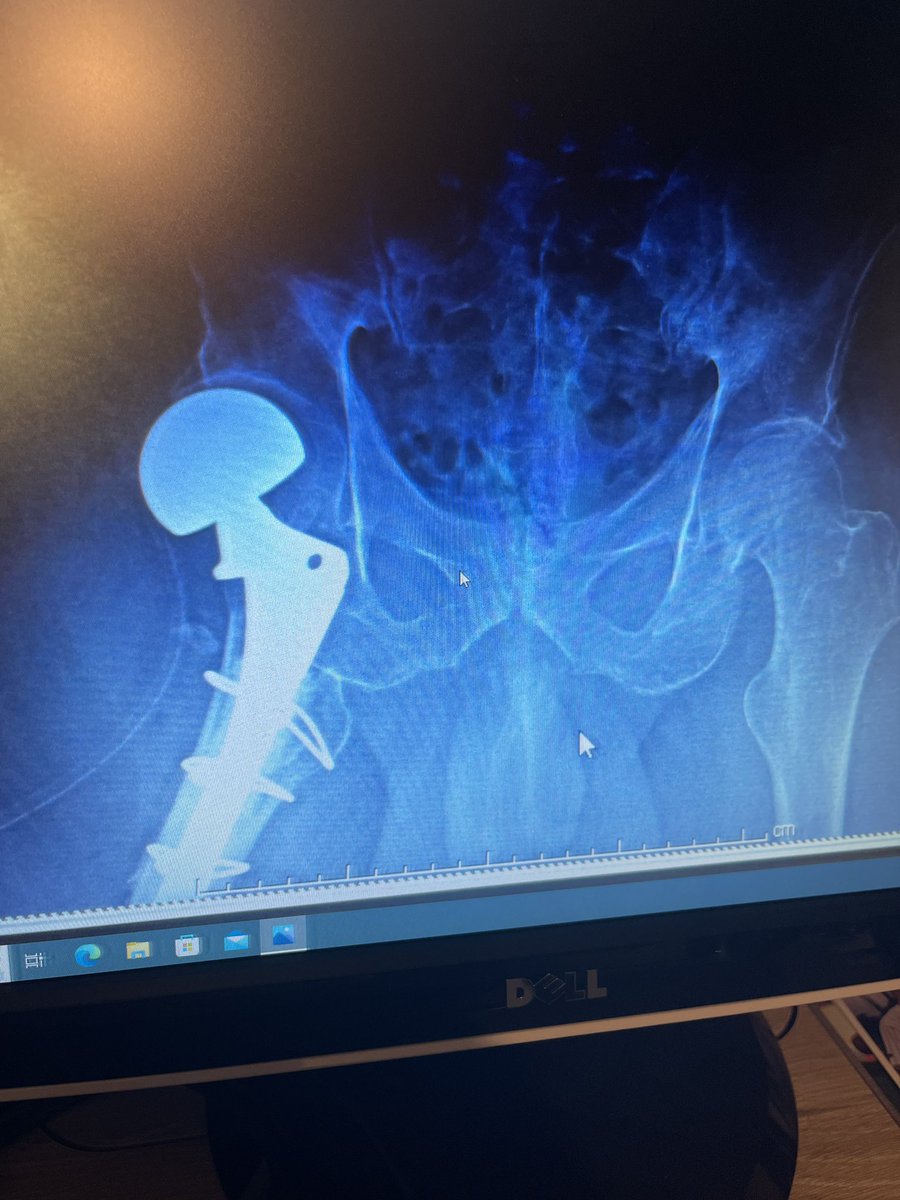

I think we found it! Thanks to @OrthoYour.

Placed backwards✔️

Cemented ✔️

Done for fracture✔️

Done in my state✔️

Done around the same time✔️